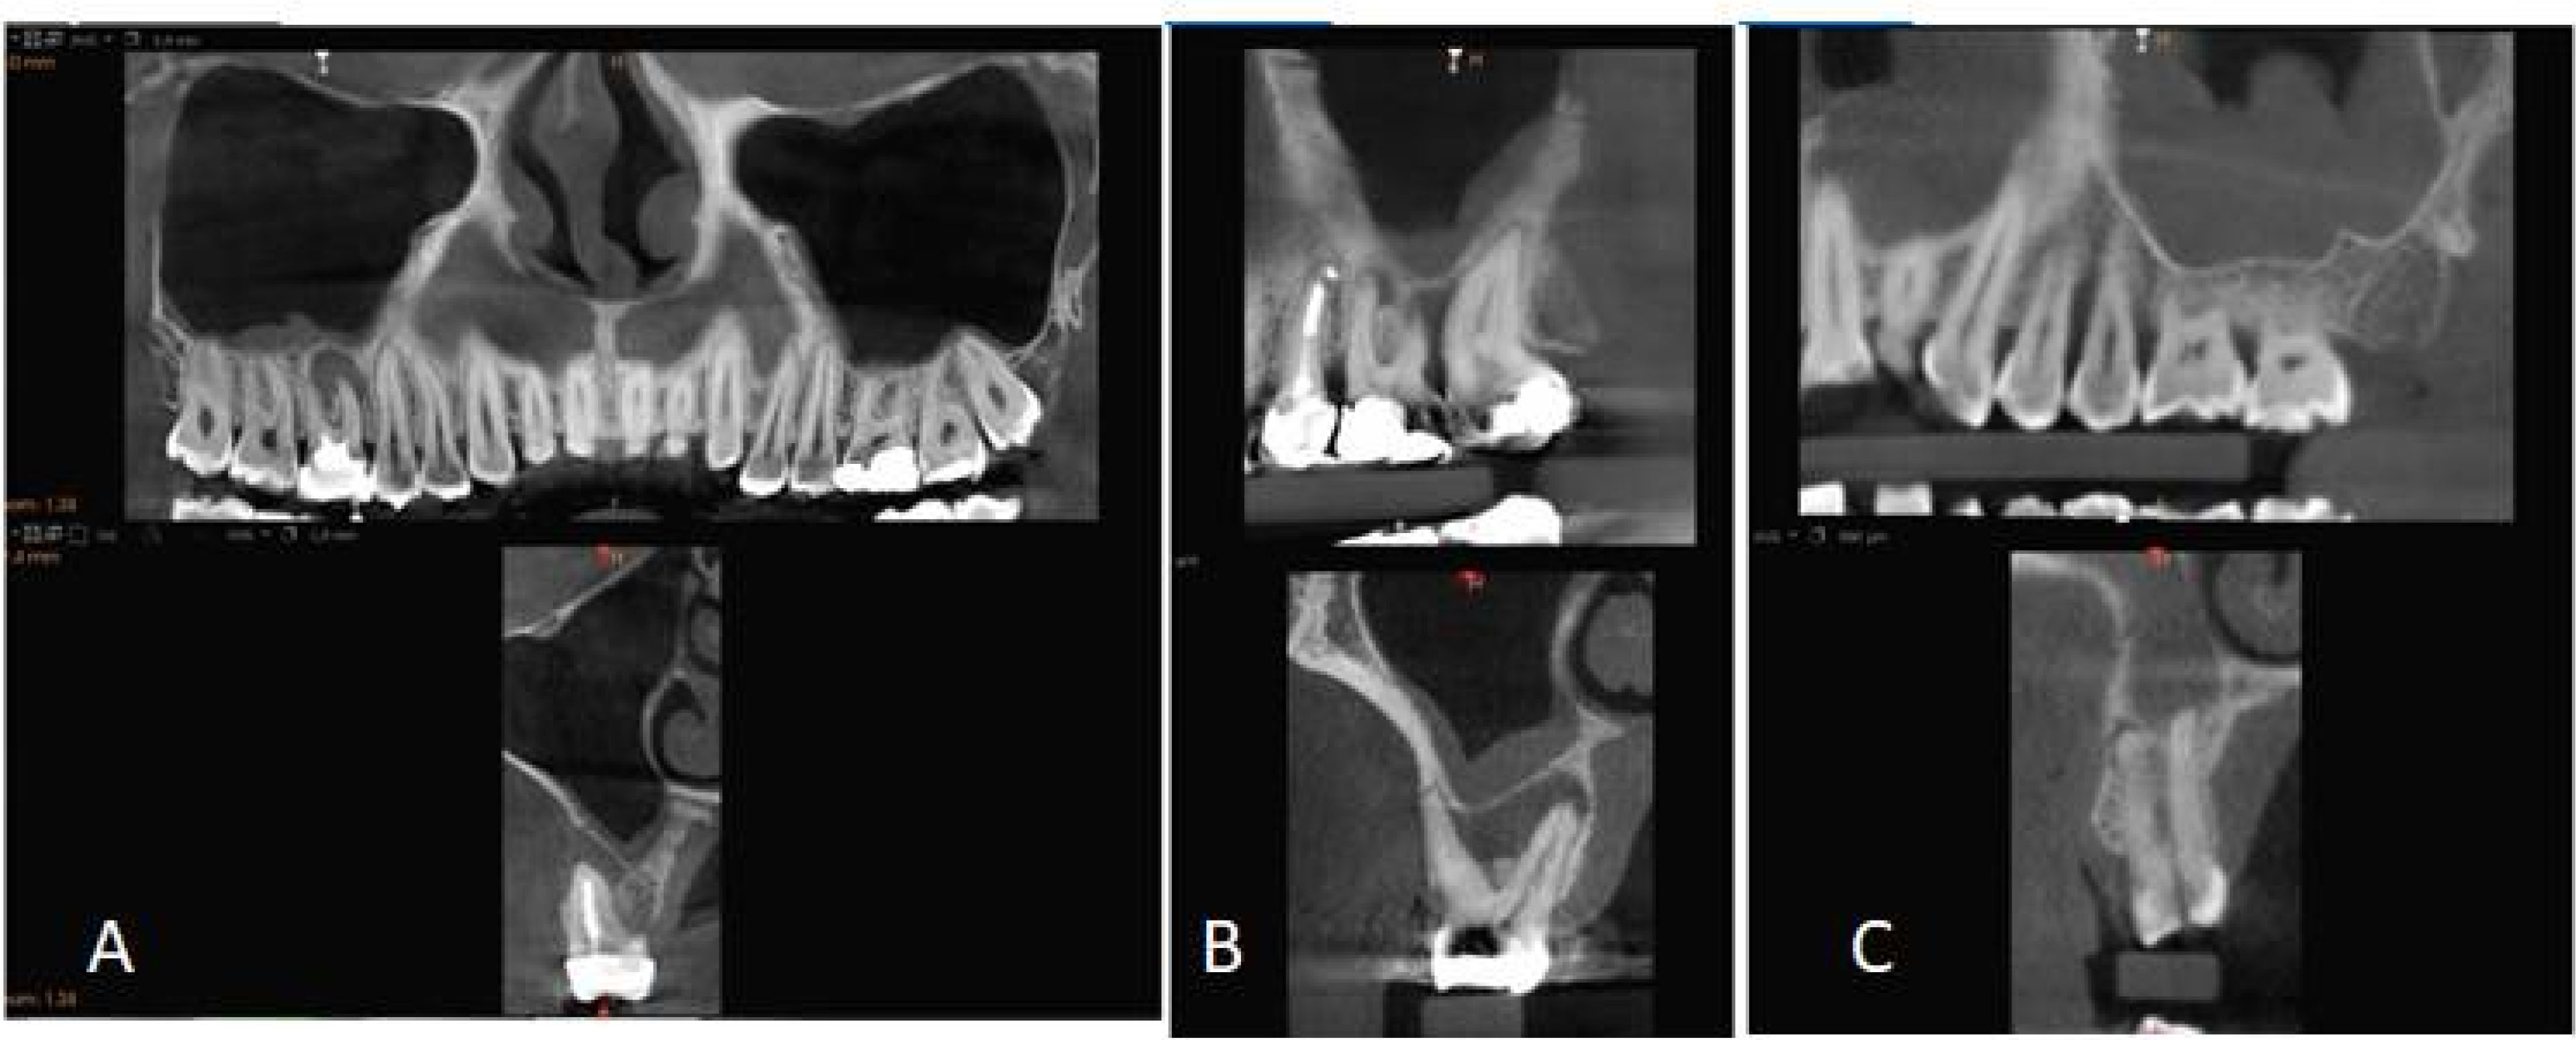

The maxillary sinuses were imaged in sagittal and coronal views, and the type of MT, MT width, and mucosal appearance (MA) of the maxillary sinuses were evaluated. The type of MT was recorded as follows: normal, local mucosal thickening (> 2 mm, limited to a maximum of two teeth), generalized mucosal thickening (> 2 mm, along the sinus floor), a dome-shaped cyst, or nonspecific opacification or fluid, periostitis, and antrolith ().

Figure 1.

A) Generalized mucosal thickening due to tooth with root canal therapy and apical periodontitis with a well-defined low-density area; B) Severe PBL and periapical lesions and mucosal thickening; C) Polypoid type mucosal thickening and fractured teeth with a periapical lesion.